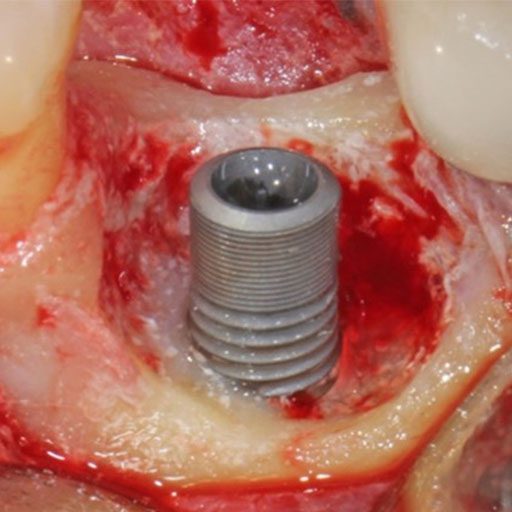

Implant Revision